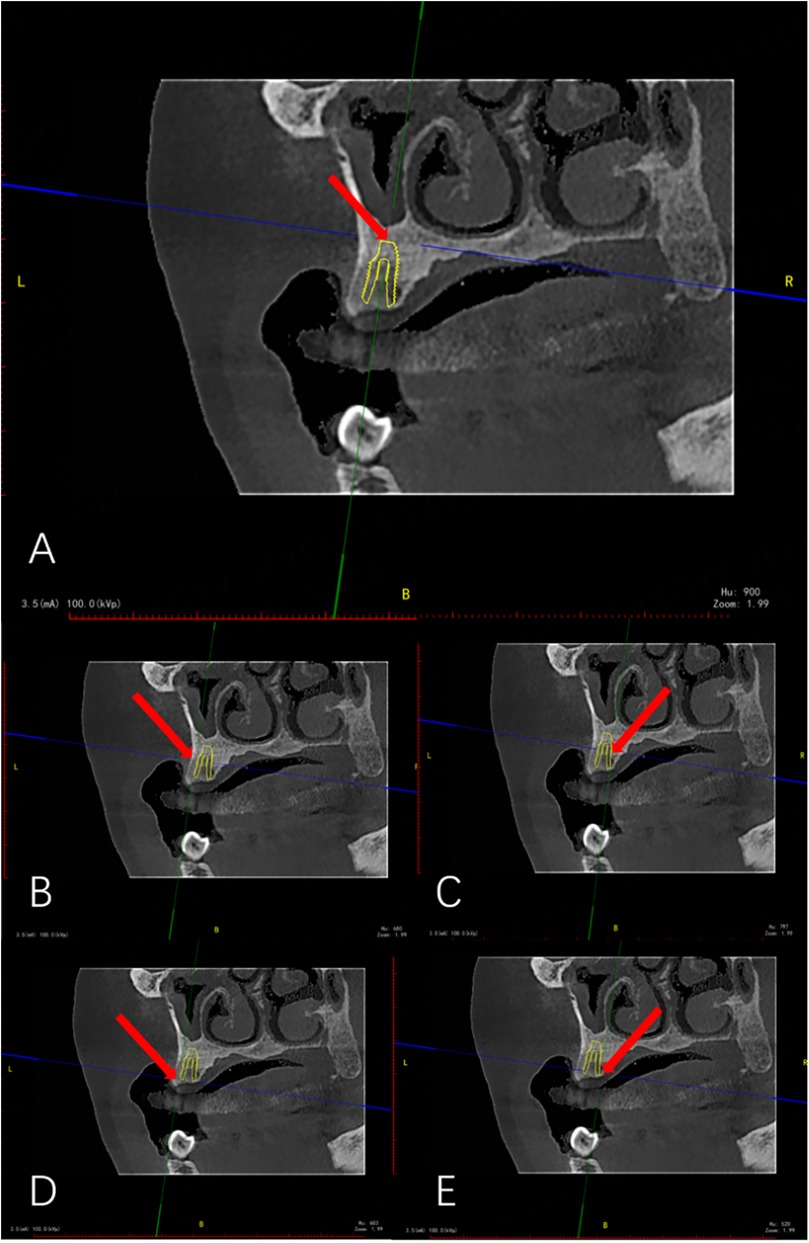

Background: Digital guided implantology improves safety and precision compared to freehand methods. A survey indicated that half-guided templates are more commonly used than full-guided ones in China. This study aims to assess the accuracy of implant placements using half-guided and full-guided digital surgical templates, considering factors like jaw location, tooth position, support type, implant timing, and bone density. Methods: 87 implants (52 half-guided, 35 full-guided) were evaluated by comparing pre-and postoperative CBCT scans to measure deviations in coronal, apical, depth, and angular positions. Bone density was also assessed in relation to the implant deviations. Results: The findings revealed that the half-guided group exhibited significantly greater deviations in several areas: maxillary angular deviations, anterior coronal and depth deviations, posterior depth deviations, tooth-supported guide depth deviations, immediate implant coronal and angular deviations, and delayed implant depth deviations (P < 0.05). No significant differences were noted in other measurements. In the bone density analysis, only the full-guided group showed a significant negative correlation between bone density and apical deviation (P < 0.05). Conclusion: Based on statistical results, power calculations, and subgroup effect sizes, the following clinical recommendations are derived: Half-guided templates, owing to their superior cost-effectiveness in fabrication time and cost, are recommended for use in mandibular posterior regions, mucosa-supported templates, delayed implantations, and clinical scenarios with uneven bone density distribution at implant sites. In contrast, full-guided templates are more suitable for maxillary implantations, anterior regions, tooth-supported templates, immediate implantations, and sites with homogeneous bone density distribution.